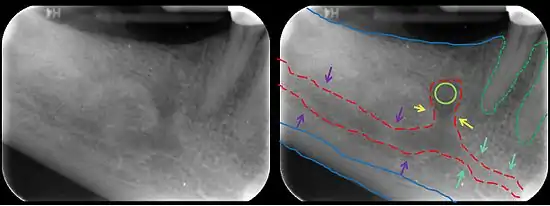

The mandibular incisive canal (indicated here by coral green arrows) continuing anteriorly (to the right) from the mandibular canal (purple arrows) after the mental foramen (light green circle)

In human anatomy, the mandibular canal is a canal within the mandible that contains the inferior alveolar nerve, inferior alveolar artery, and inferior alveolar vein. It runs obliquely downward and forward in the ramus, and then horizontally forward in the body, where it is placed under the alveoli and communicates with them by small openings.

On arriving at the incisor teeth, it turns back to communicate with the mental foramen, giving off a small canal known as the mandibular incisive canal, which run to the cavities containing the incisor teeth.[1] It carries branches of the inferior alveolar nerve and artery.

The mandibular canal is continuous with tow foramina: the mental foramen which opens in the mental region of the mandible and carried the distal fibres of the inferior alveolar nerve as the mental nerve; and the mandibular foramen on medial aspect of ramus, into which the mandibular nerve enters to become the inferior alveolar nerve. The mandibular canal often runs close to the apices of the third molar tooth, and the inferior alveolar nerve can become damaged during removal of this tooth, causing sensory disturbance in the distribution of the nerve. This is sometimes the case for the second or first molar teeth, and care must be taken during removal or root canal treatment in such cases to prevent nerve injury or extrusion of root canal filling materials.[2]